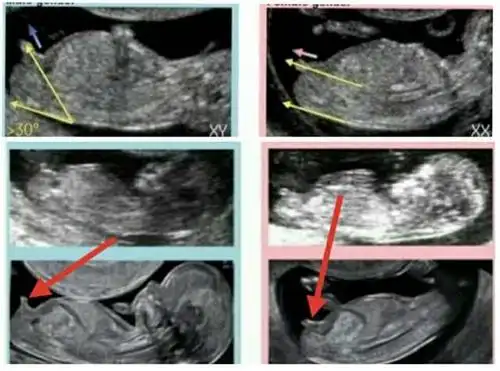

nt图有三条线是女孩怀孕12周nt图女孩的标志

nt数值怎么看男女

12周3天的nt图看男女,有会看的姐妹帮看看吗